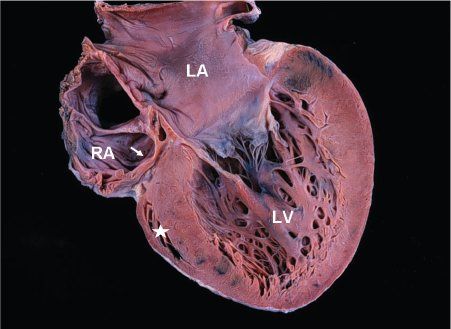

Tricuspid atresia is the third most common form of cyanotic congenital heart disease, with a prevalence of 0.3% to 3.7%, and is characterized by absence of a direct communication between the right atrium (RA) and the RV (Fig. 12.1). There is a univentricular AV connection with the dominant ventricle having left ventricular morphology. The anatomic form of atresia is most commonly fibromuscular; less commonly, it is membranous, valvar, or Ebstein-like with valvar atresia. In the majority of patients, the floor of the RA is entirely muscular with separation from the hypoplastic RV by fibrofatty tissue. Although we use the term “tricuspid atresia” for lesions with an echogenic plate-like area beneath the floor of the right atrium and above the right ventricle, this echogenicity is usually not the result of an atretic tricuspid valve but rather it results from fibrofatty tissue in the AV groove. Therefore, tricuspid atresia is likely a result of failure of formation of the tricuspid valve rather than fusion of formed tricuspid valve leaflets. True atresia of tricuspid valve leaflets as seen in the atretic tricuspid valve in Ebstein anomaly is rare.

Figure 12.1. Pathologic specimen in tricuspid atresia showing the atretic fibrofatty tricuspid valve (arrow). The left atrium (LA) and left ventricle (LV) are enlarged. The right ventricle is extremely hypoplastic and appears as a “slit-like” space (asterisk). RA, right atrium.